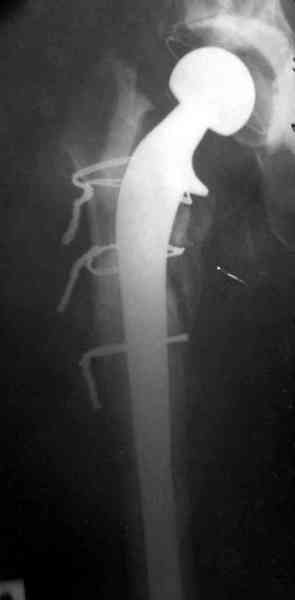

Повторная операция по удалению тотального протеза с irrigation&debridment, канал после очистки цемента обильно промыт и рассверлен римером.

Приготовлен цемент из расчета: Tobramycin 2.4 g (2 флакона), Vancomycin 2 млн (4 флакона) и 2 упаковки цемента с добавлением дополнительного флакона цементной жидкости.

После обработки ацетабулярного компонента, ещё в мягком цементе в полости вертлужной впадины головкой бедренного компонента сделана выемка для головки, чтобы свежий цемент не прилипал к головке. Головку бедренного компонента завернул обычной стерильной фольгой, которую после образования выемки отлепил от головки.

Для спейсера в бедро использовал старый длинный бедренний компонент меньшего диаметра, облепленный со всех сторон цементом с антибиотиком.

№3-6 снимки с осложнением

и последние снимки.